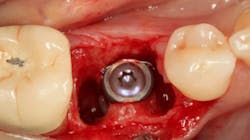

Excellent interseptal bone width was present, both buccal and lingual plates were present, and an adequate amount of bone was present coronal to the inferior alveolar nerve to allow for immediate implant placement. A sulcular incision was made around K and the adjacent teeth, and a full-thickness buccal and lingual flap was reflected. The tooth was sectioned in half, and the mesial and distal roots were elevated. The socket was degranulated with a round diamond bur and copiously irrigated with chlorhexidine gluconate 0.12% rinse. An osteotomy was completed in the interseptal area, and a bone-level 4.8- x 10-mm implant was placed to 35 Ncm. A mixture of cancellous and cortical allograft was infused with autogenous plasma-rich growth factor (PRGF), which was isolated during a preprocedural blood draw. The mixture was packed into the residual socket, slightly coronal to the implant platform to account for predictable resorption during healing. (13)

A 15- x 20-mm Ossix Plus membrane was hydrated in sterile saline for three minutes and trimmed to extend roughly 3 mm beyond the buccal and lingual extent of the bone graft and roughly 1 mm from the adjacent teeth. A sterile template is included in each membrane package; it can be trimmed to the appropriate dimensions and superimposed on the Ossix Plus membrane for final trimming to ensure the exact dimensions desired are obtained. This membrane can also be sutured, if necessary. When this technique is used, it is important to pass the suture needle through the membrane at a 90-degree angle to avoid tearing the membrane.

In this case, I placed an autogenous fibrin clot, which was isolated from the fractionated blood draw, over the Ossix Plus membrane and sutured, without obtaining primary closure, using a CV-5 Gore-Tex (W.L. Gore & Associates Inc.). This technique is designed to help facilitate the formation of a blood clot over the Ossix Plus membrane. It can be used with the addition of a collagen plug over the membrane, or you can just suture and allow a natural clot to form.